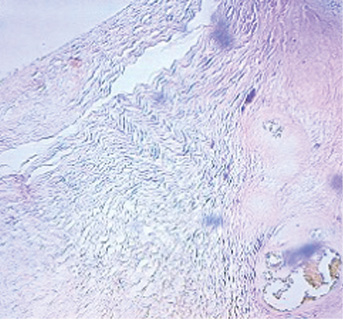

Через 6 мес от начала эксперимента

Контрольный сустав (правый): не наблюдается значительных изменений, движения в суставе ограничены, глубина кратера «минус-ткань» составляет около 3/5 толщины здорового хряща, края не сглажены, граница между новообразованной тканью и сохранённым хрящом прослеживается чётко. Микроскопически процесс регенерации хрящевой ткани носит незавершённый характер. Субхондральная костная пластинка и субхондральная губчатая кость уплотнены и утолщены, выступают в сторону поверхности.

1-я экспериментальная группа (левый сустав): наблюдается ограничение движений в суставе, определялась «минус-ткань», которая составляет 1/2 толщины сформированного дефекта. Края гладкие ровные, граница между новообразованной тканью и сохранённым гиалиновым суставным хрящом прослеживается чётко. Микроскопически полной регенерации хряща не происходит. Полость остеохондрального дефекта мыщелка заполнена незрелой хрящеподобной тканью. Субхондральная костная пластинка восстановлена на всём протяжении, за исключением области в центральном отделе дна сформированного дефекта.

2-я экспериментальная группа (левый сустав): движения в суставе частично ограничены, определяется «минус-ткань», составляющая около 1/4 толщины сформированного дефекта, с ровными гладкими краями, граница между новообразованной тканью и сохранённым гиалиновым суставным хрящом прослеживается чётко, поскольку новообразованная ткань умеренно полнокровна. Микроскопически в области дефекта формируется незрелая хрящевая ткань. Хондроциты более дифференцированы. Наблюдается интенсивный рост хряща по аппозиционному типу. Субхондральная костная пластинка неравномерно восстановлена, определяется между губчатой костью и соединительной тканью, форма её извилистая.

3-я экспериментальная группа (левый сустав): ограничений движения в суставе нет, дефект практически полностью восстановлен, граница между новообразованной тканью и хрящом сглажена, края ровные. Микроскопически полость дефекта полностью заполнена зрелой хрящевой тканью типа гиалинового хряща. Субхондральная костная пластинка восстановлена на всём её протяжении.

За 6 мес во всех группах произошли макро- и микроскопические изменения, представленные в табл. 3.